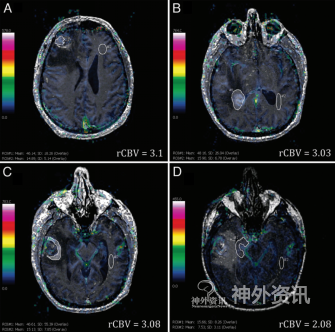

患者47岁,系多发性胶质母细胞瘤。主要症状是下肢无力,易摔倒,直立时右侧进行性头痛;查体显示神志清,左下象限偏盲,无记忆力和语言障碍。曾因椎管狭窄行腰椎板切除术。头颅CT发现右侧半球有多处病变,增强MRI提示病变分别位于右额叶、右枕角区和右颞叶(图1)。

图1. 患者术前MRI,利用相对脑血容量、动态增强成像。右侧额叶(A)、右枕角区(B) 、右侧颞叶(C)和右侧海马(D)处多发肿瘤。